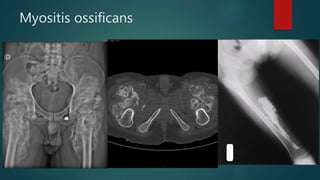

Myositis ossificans

• #96 Hypertrophic phenomena and gross heterogeneous muscle calcifications that extend from the pelvis to the middle third of the thighs. A firearm projectile is located in the soft tissues in left inguinal region. Notice that the bone cortical isn't affected Myositis ossificans is a benign process characterised by heterotopic ossification usually within large muscles. The diagnosis is usually based on the patient's history (of trauma),